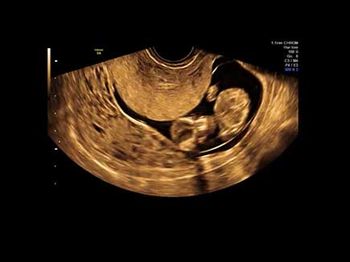

Challenge your diagnostic skills: Can you identify this anomaly?